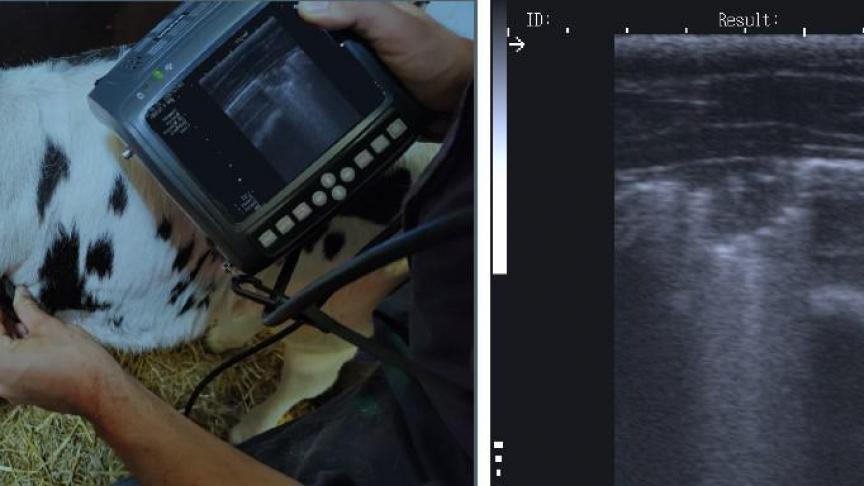

Een betrouwbare manier om deze verborgen gevallen op te sporen, is snelscan longechografie (quick thoracic ultrasound - qTUS). Met deze techniek kan een dierenarts in amper 1 à 2 minuten vaststellen of er sprake is van pneumonie (longontsteking) en kan hij een onderscheid maken met ontstekingen van de bovenste luchtwegen. Gezien pneumonie vaak bacterieel van oorsprong is, is het behandelen van dieren met een longontsteking met antibiotica een logische vervolgstap.

Toch is dit vaak minder eenvoudig dan gedacht. Zo is M. bovis van nature ongevoelig voor penicilline-achtigen en trimethoprimsulfonamiden. Eerstelijnsproducten, zoals florfenicol en oxytetracycline, lijken betere alternatieven, vooral bij vroege detectie. Dit blijkt ook uit een studie waarbij longechografie werd gebruikt om de behandeling te begeleiden tijdens een uitbraak van M. bovis op een gesloten vleesveebedrijf. Hierbij werd aangetoond dat dankzij longechografie en gerichte behandeling meer dan 95% genezing bereikt werd na 7 dagen, met halvering van het antibioticagebruik. Bovendien werd door individueel te behandelen bijna de helft minder antibiotica gebruikt dan bij een standaard groepsbehandeling van 7 dagen. Longechografie maakt zo een vroegtijdige diagnose mogelijk, wat leidt tot een hogere kans op genezing en een lager antibioticagebruik. Binnen het project wordt deze techniek, in combinatie met diagnostiek, dan ook ingezet om meer inzicht te krijgen in het verloop van behandelingen en om na te gaan of genezen dieren ook effectief stoppen met het uitscheiden van de kiem.